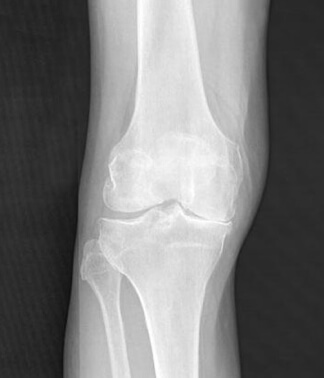

RTG desnog kolena Milane Topić nakon tretmana preparatom Herbolo.

U slučaju naše pacijentkinje Milane Topić, pozitivna dinamika primećena je od prvih dana primene: Oteklina i bol su se smanjili. Krajem druge nedelje pacijent se nesmetano kretao i bez pomoći bolničkog osoblja. Na kraju lečenja, degenerativni zglob se oporavio do stanja zdravog zgloba. Njegova prirodna pokretljivost se potpuno vratila. I sve to bez injekcija, operacija i drugih metoda. Do pre nekoliko godina takav rezultat se mogao dobiti samo protezom.